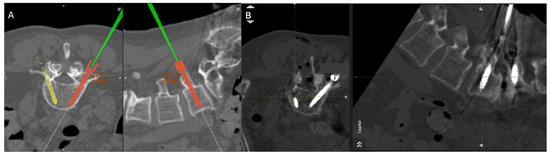

2.2. Surgical Approach

- The navigated screw with the screw driver is calibrated.

- A final intraoperative CT is completed with the navigation reference in place in case of further instrument adjustment or decompression.

3.2. Screw Placement and Accuracy